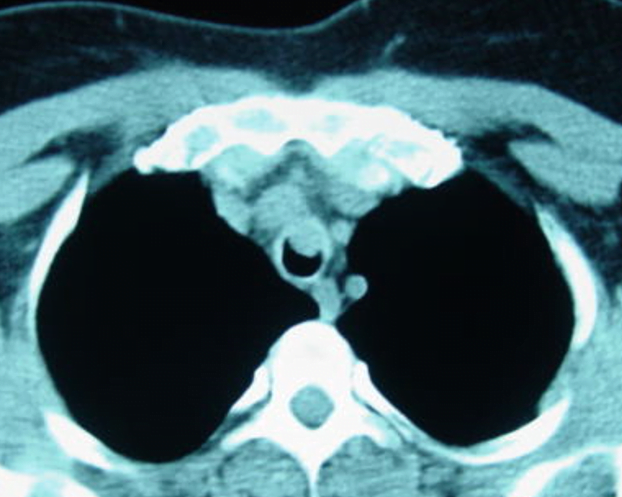

Trakea Tümörleri

Öksürük, wheezing ve stridor, dispne, hemoptizi, ses kısıklığı, disfaji, rekürren pnömonilerdir.   Trakea tümörü semptomları yalnızca trakea tümörleri özgü olmadığından tanı yanlışlığı ve gecikmelere neden olabilir.  Bu hastalar astım ve KOAH hastaların şikâyetlerini taklit ettiği için bir kısmı astım diye takip edilip sonradan tanı konan bir çok hasta var.